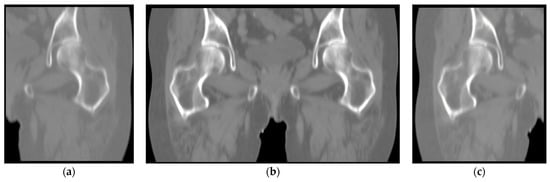

Figure 2 displays the coronal images viewed from the anterior side. The complete image (b) is shared between the two datasets, and as a complement, each of the two datasets also contains unique left femur (a) and right femur (c). In this way, we can simply expand the dataset and accurately distinguish between left and right femur when segmenting CT images that contain a complete structure. By removing the data with poor image quality, in Dataset A, we ended up with 112 images of the left femur, of which 84 images were used for training, and 28 images formed the validation set. Similarly, 113 images were collected in Dataset B. A total of 85 images were used for training, and 28 images were used for validation. Subsequently, manual annotation of the femur for the constructed dataset.

Figure 2.

Coronal images viewed from the anterior side: (a) left femur; (b) images shared by both datasets; (c) right femur.